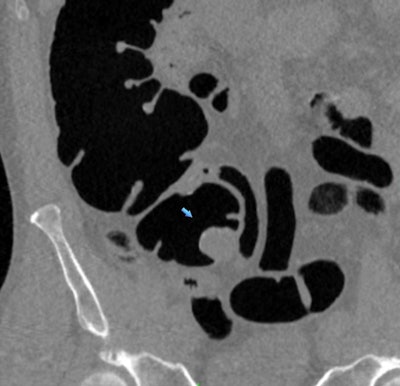

Believing that ample data already existed that simply needed to be aggregated and analyzed, Pickhardt and colleagues examined the results of 34 studies published between January 1994 and August 2017 that included 18,798 seniors who underwent CTC screening for colorectal cancer. CTC's positive screening rates for large polyps or cancers ranged from 9% to 31%, with a sensitivity of 93%, and it had a positive predictive value of 84.3% for advanced colorectal cancer (AJR, April 18, 2018).

In addition, the researchers found a statistically significant increase in cancer detection rates for Medicare-age individuals (65 years and older) compared with younger adults.

The cancer detection rates increased even more to 14% (p = 0.013) for patients who demonstrated symptoms of cancer before undergoing screening and to 32.8% (p < 0.001) for those with positive results on fecal occult blood tests.

To boost the cost-effectiveness of CTC screening without missing cancerous lesions, the group settled on a cutoff size of 10 mm for lesions requiring follow-up colonoscopy. This threshold had a high sensitivity for cancer detection and a high yield for advanced cancer while also keeping the referral rate after screening to below 10% -- making it highly cost-effective, Pickhardt said.